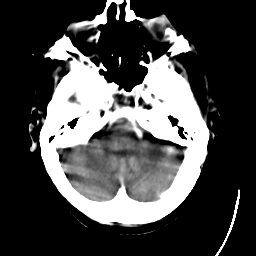

Meningioma: Roentgen-ray CT #1 -- Slice #3

[Home][Help][Clinical] Slice 3